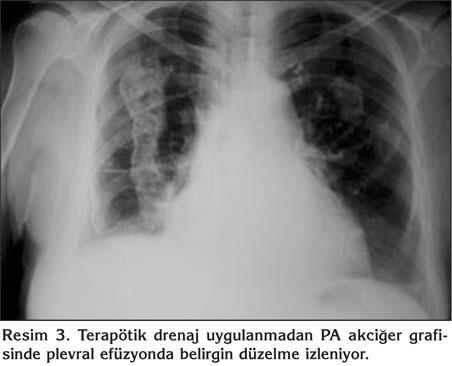

Yetmi? iki ya??nda, hipertansiyon ve atriyal fibrilasyon tan?lar?yla takip edilen hasta bir hafta ?nce ba?layan nefes darl???, ?ks?r?k ve sa? yan a?r?s? yak?nmalar?yla ba?vurdu. Ek hastal?k ve travma ?yk?s? bulunmayan hastan?n ?z ge?mi?inde ?evresel asbest maruziyeti mevcuttu. Fizik muayenede arteryel kan bas?nc? 100/60 mmHg ve nab?z 97/dakika-aritmikti. Sa? hemitoraksta skapula alt?nda solunum sesleri, vibrasyon torasikte azalma ve perk?syonda matite saptand?. Arter kan gaz? analizinde PaO2: 65 mmHg, PaCO2: 34 mmHg, pH: 7.46 ve SaO2: %95 idi. Laboratuvar incelemesinde Hb: 14.7 g/dL, Htc: %44.3, trombosit: 456 x 103/dL, l?kosit: 8.5 x 103/dL, eritrosit sedimentasyon h?z? 60 mm/saat idi. Kan biyokimyas? ve idrar analizi normaldi. Atriyal fibrilasyon nedeniyle warfarin tedavisi alan hastada PT: 111.5 saniye (N: 9.4-12.5 saniye) ve INR de?eri 8.85 (N: 0.82-1.07) olarak bulundu. G???s radyografisinde sa? alt zonda plevral ef?zyon ile uyumlu opasite ve d?zensiz s?n?rl? plevral plaklar izlendi (Resim 1). Ba?ka bir merkezde ?ekilen toraks bilgisayarl? tomografi anjiyografide tromboemboli ile uyumlu bulgu yoktu ve sa? akci?erde en kal?n yerinde 8 cm ?l??len plevral ef?zyon ve kom?ulu?unda subsegmenter atelektazi ve her iki akci?er ?st lob ve alt lob plevras?nda en kal?n yerinde 15 mm olan d?zensiz plevral kal?nla?ma ve kalsifik plaklar izlendi (Resim 2). Warfarin tedavisi kesilerek K vitamin replasman? yap?ld?. Normal INR d?zeyi sa?lanan hastaya tan?sal torasentez yap?ld? ve yakla??k 40 cc defibrine hemorajik s?v? aspire edildi. Plevral s?v? k?lt?r?nde ?reme olmad?. Sitolojik incelemede periferik kan elemanlar? aras?nda histiyosit ve reaktif mezotel h?creleri izlenen olguda, plevral s?v? hematokriti kan hematokritinin %50'sinden b?y?k saptanmas? ?zerine hemotoraks tan?s? konuldu. Hemotoraks miktar?n?n az olmas?, p?ht?l? olmamas? ve spontan olarak geriledi?inin izlenmesi nedeniyle drenaj yap?lmad?. Takiplerinde radyolojik d?zelme izlenen hasta komplikasyonsuz taburcu edildi (Resim 3).

Resim 1